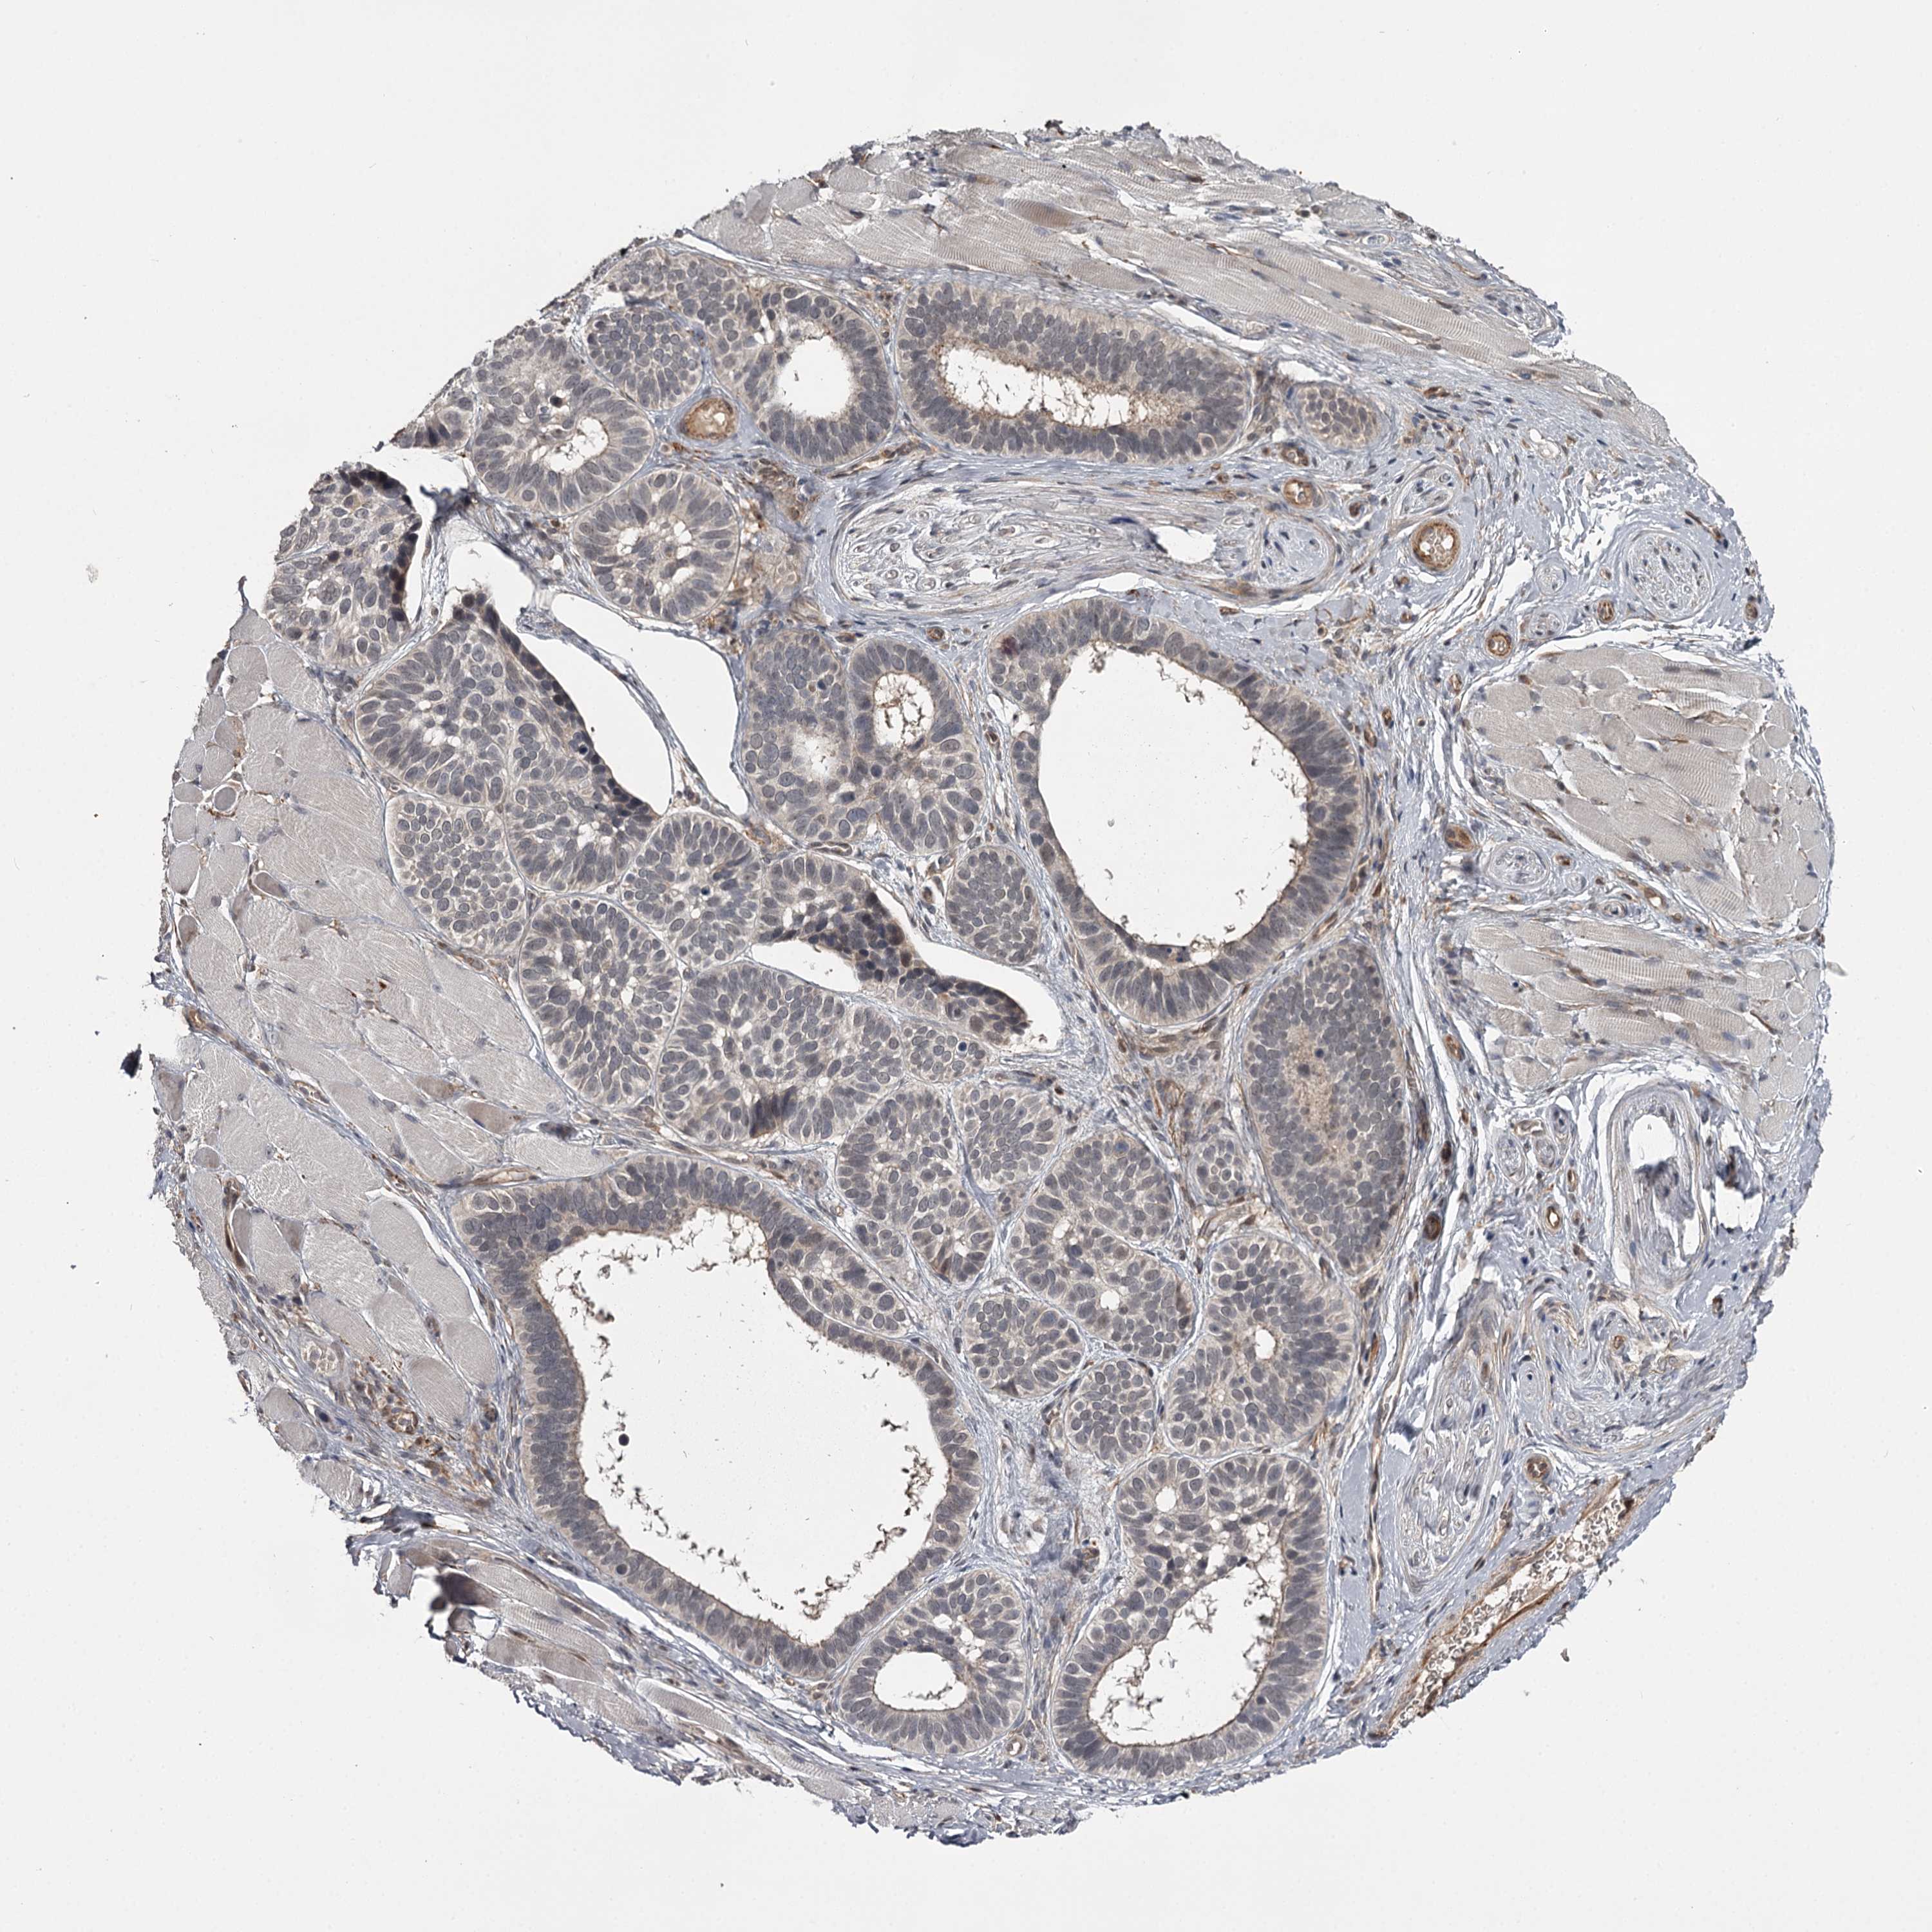

SKIN CANCER - Protein expressioni

A mouse-over function shows sample information and annotation data. Click on an image to view it in a full screen mode. Samples can be filtered based on level of antibody staining by selecting one or several of the following categories: high, medium, low and not detected. The assay and annotation is described here.

Antibody stainingi

Antibody staining in the annotated cell types in the current human tissue is reported as not detected, low, medium, or high, based on conventional immunohistochemistry profiling in selected tissues. This score is based on the combination of the staining intensity and fraction of stained cells.

Each image is clickable and will lead to virtual microscopy that enables deeper exploration of all samples and also displays staining intensity scores, fraction scores and subcellular localization as well as patient and tissue information for each sample.

Antibody HPA038166

Staining

High

Medium

Low

Not detected

Intensity

Strong

Moderate

Weak

Negative

Quantity

>75%

75%-25%

<25%

None

Location

Nuclear

Cytoplasmic/membranous

Cytoplasmic/membranous,nuclear

Basal cell carcinoma

Squamous cell carcinoma, NOS

Squamous cell carcinoma, metastatic, NOS